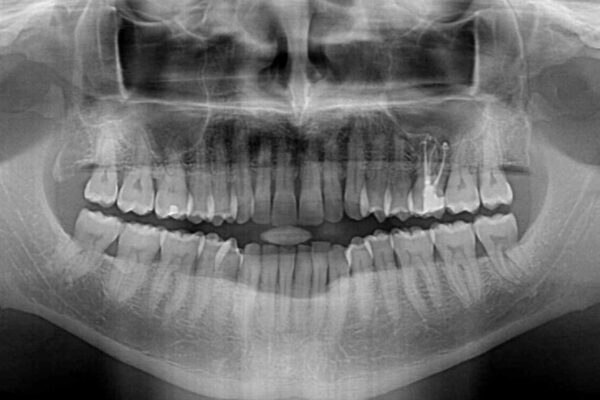

治療途中

• 前歯でものを噛みきりたい 目立たない装置でのワイヤー矯正 治療途中画像